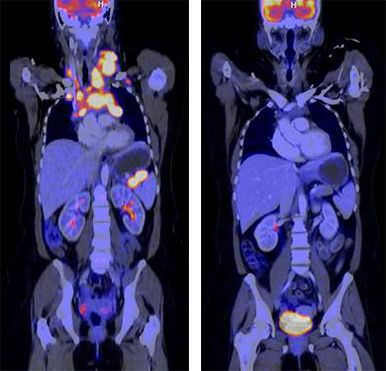

FDG-PET/CT, Mb. Hodgkin, vor/nach Chemotherapie

Die Methoden der Hybrid-Bildgebung (PET/CT und PET/MRT) gehören zu den modernsten bildgebenden Verfahren und werden insbesondere zur Tumordiagnostik eingesetzt. Der große Vorteil der Hybrid-Bildgebung ist die Kombination einer funktionellen Methode (PET, Positronen-Emissions-Tomographie) mit einer morphologischen Bildgebung (CT - Computertomographie oder MRT - Magnetresonanztomographie) in einem Untersuchungsgang. Man erhält so gleichzeitig Informationen über Funktionen (z.B. Stoffwechsel) und zu Strukturen von gesundem oder krankem Gewebe im Körper.

Die PET ermöglicht mit hoher Sensitivität und Spezifität kleinste Stoffwechselveränderungen nachzuweisen. Hierfür werden schwach radioaktiv markierte Substanzen (sogenannte Radiopharmaka) eingesetzt, die spezifisch Stoffwechselveränderungen von Erkrankungen nachweisen oder gegen Antigene gerichtet sind. PET ist damit die genaueste Methode, um nicht-invasiv molekulare Veränderungen abzubilden.